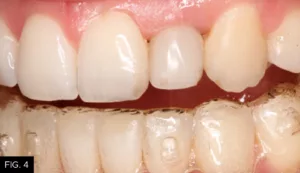

The periodontist extracted the failing #10, immediately placed a 4/3 x 15 mm endosseous implant (Biomet 3i), and performed a soft tissue augmentation procedure to achieve maximum gingival esthetics.6 With the healing cap in place, the clear aligners were fitted with a custom pontic to replace the extracted #10 for three to four months. Once the periodontist confirmed implant integration, impressions were taken to create a temporary crown on the implant. The surgeon then refined the soft tissue augmentation and the temporary crown was modified to ensure optimal esthetics (FIG. 4-5b).5,7

The healing time for the temporary crown was six months, during which time the patient was instructed to wear his aligners nightly. Once tissue healing was achieved (FIG. 6), the temporary crown was removed, and an implant transfer was placed and verified with a periapical radiograph. (FIG. 7)